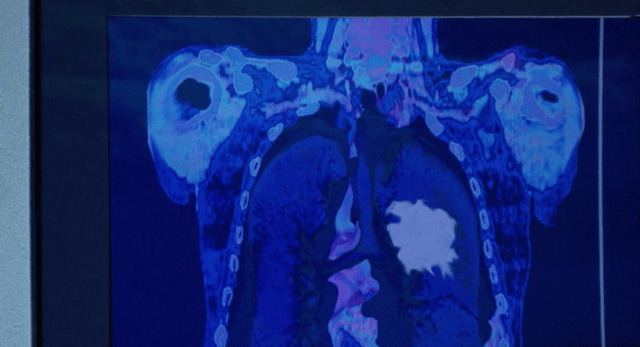

Walter (Bryan Cranston) is at the doctor with his family in town. Everybody’s there, from Skyler (Anna Gunn) and Junior (RJ Mitte) to both Hank (Dean Norris) and Marie (Betsy Brandt). They’re all waiting for his next results from a PET-CT. I have to mention, I love Marie – she is incredibly annoying and ignorant at times, but she is loving, and only wants the best at all times for her family.

But now Walt is back at the doctor’s office with the whole gang. Even better, the results of his scan are positive. Remission is possible now; his tumour shrank by 80%. A stark contrast from where he was just previously, believing he was on the verge of death. Everybody else is happy. Except for Walt. He’s happy, just not ecstatic. He almost wanted for things to go on as they were. Now he’s faced with living, moving on, and how could that work with what he’s brought into his life?